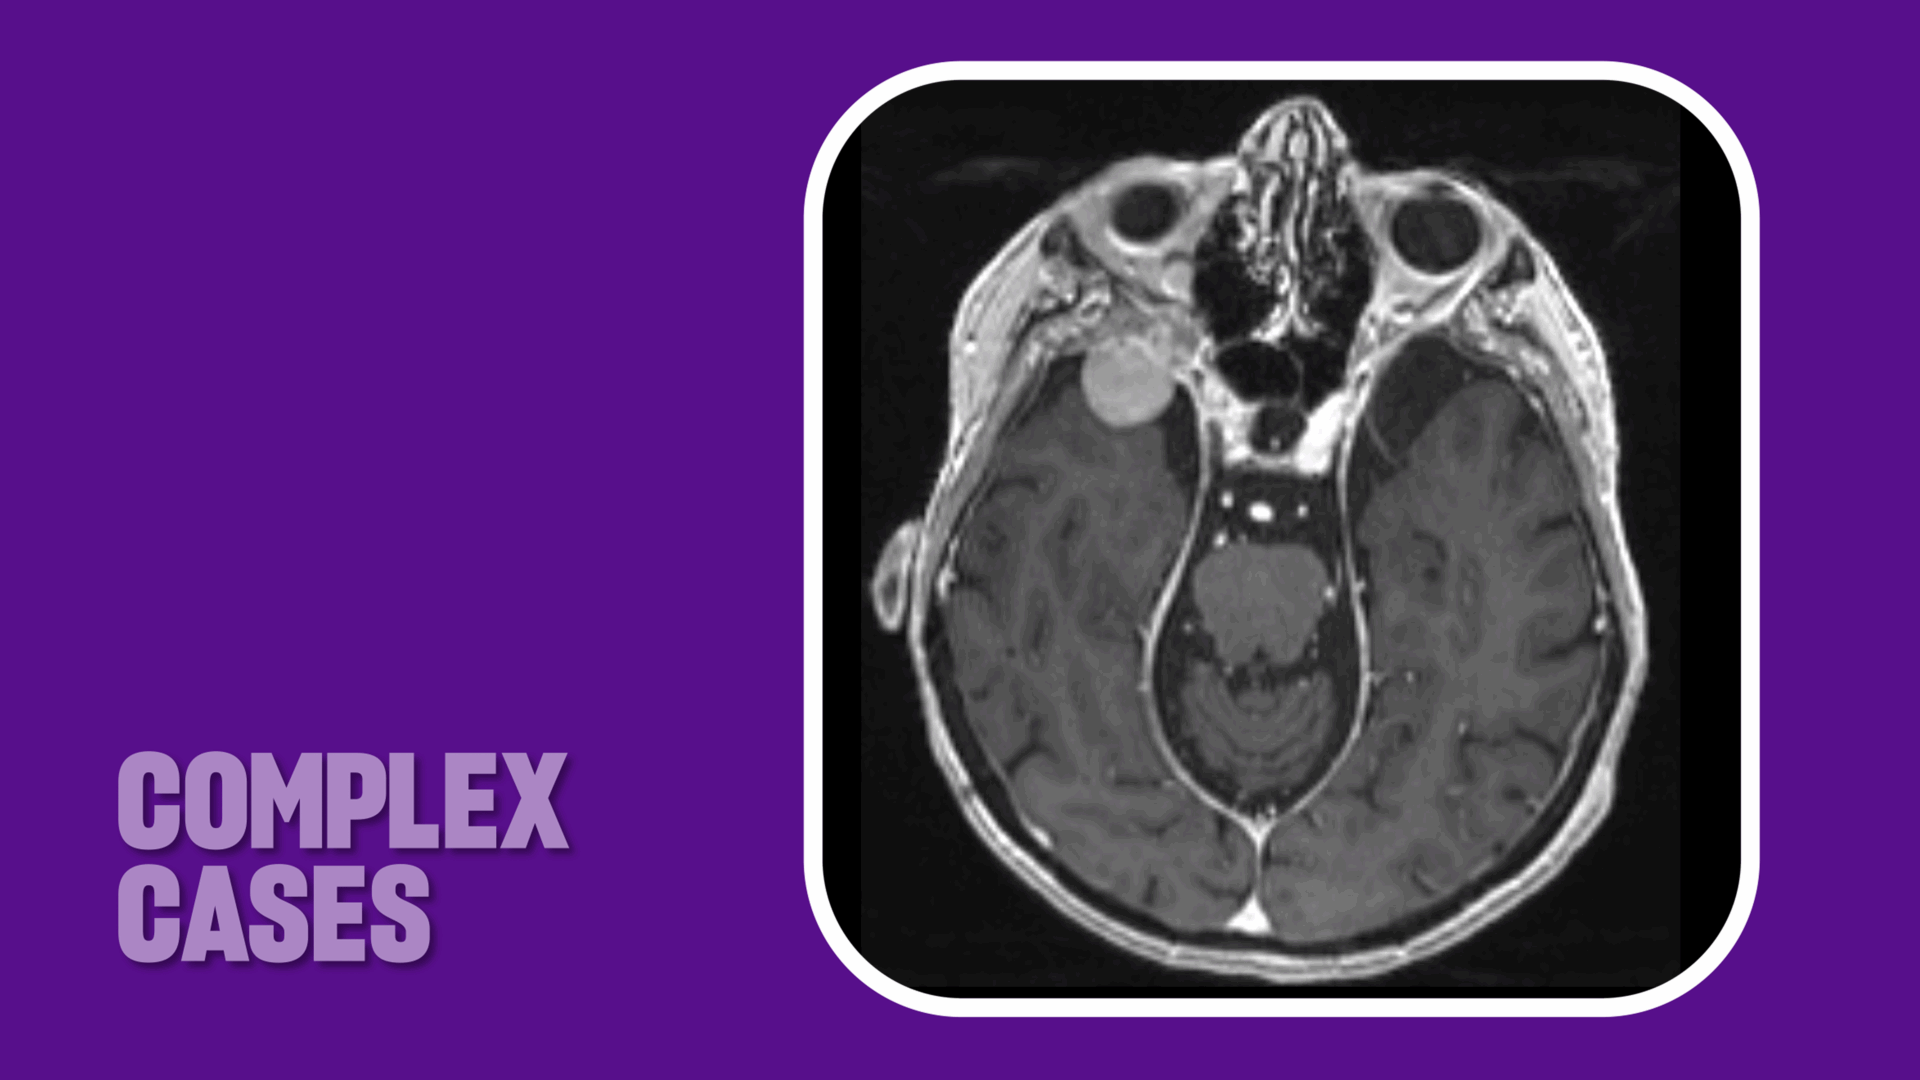

“Radiographic imaging revealed that the spheno-orbital meningioma had grown significantly, causing compression of the optic nerve,” says neurosurgeon Donato R. Pacione, MD, attending physician on the case. “The tumor was extending from the orbit and the orbital apex into the middle cranial fossa and intracranial space. It was up against the anterior temporal pole, with a tail at the level of the cavernous sinus.”

Other notable features included markedly pneumatized frontal and ethmoid sinuses that extended over the orbit and tracked along the proximal orbital roof, nearly reaching the level of the sphenoid wing.